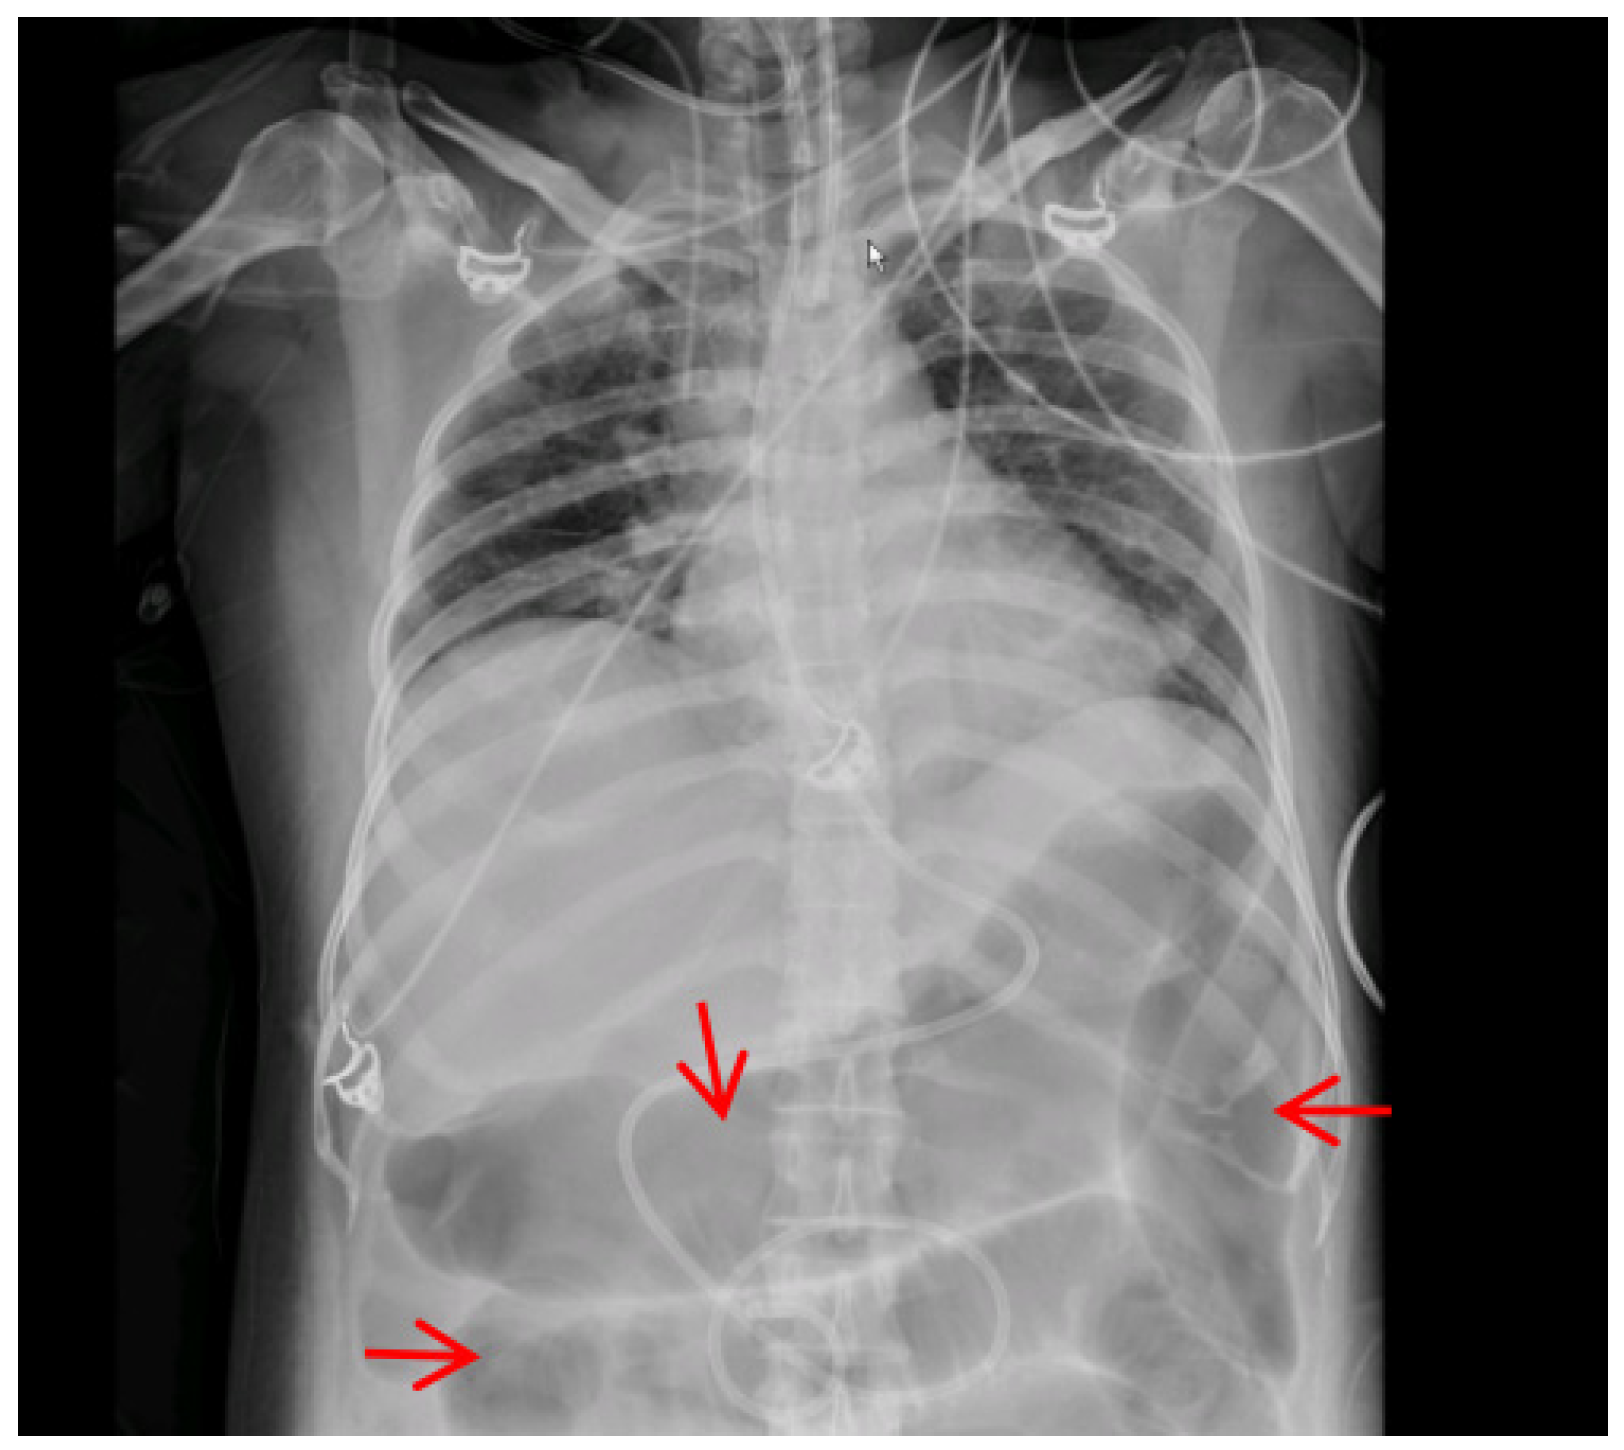

| Paralytic ileus | 1 (4) | 0 (0) | 1 (100) | 0.1852 |